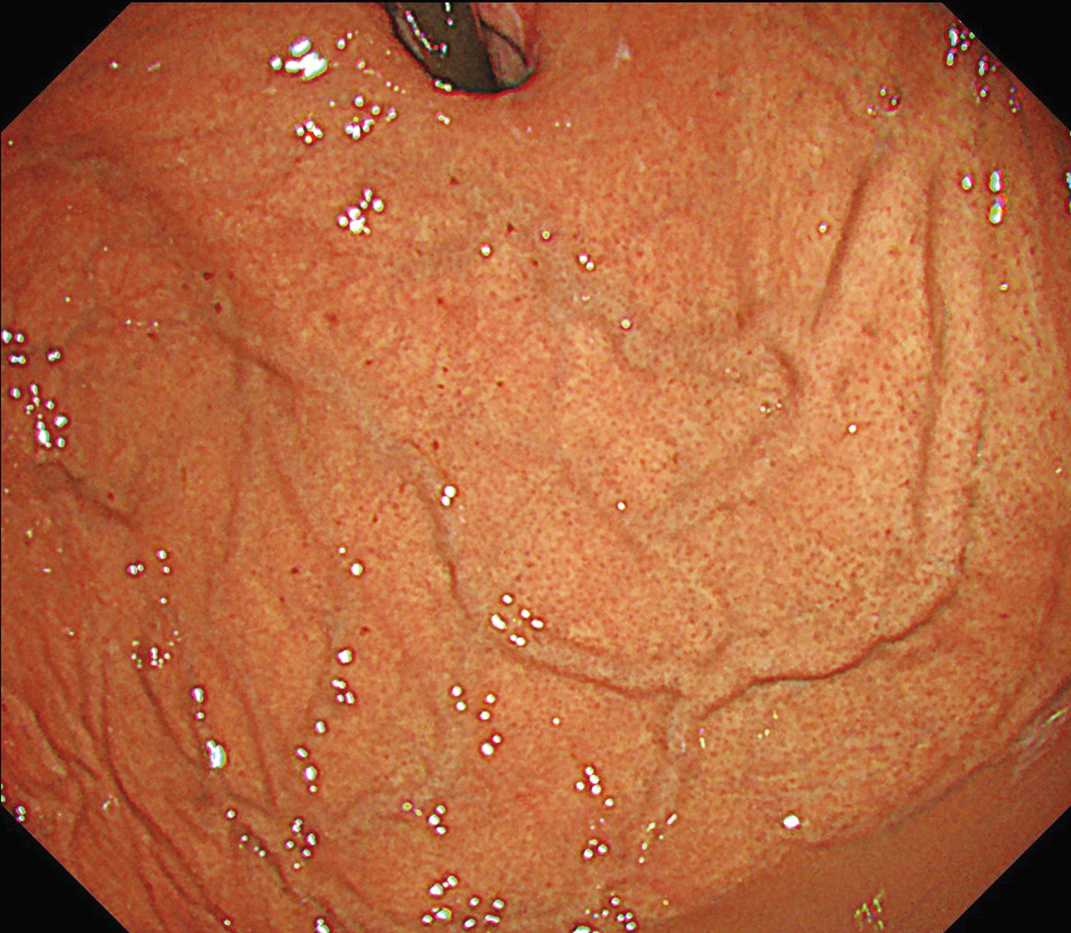

EVIS X1×GIF-1200N 症例画像

胃体部 見下ろし観察

1視野で体上部から胃角まで明るい視野での観察に貢献する